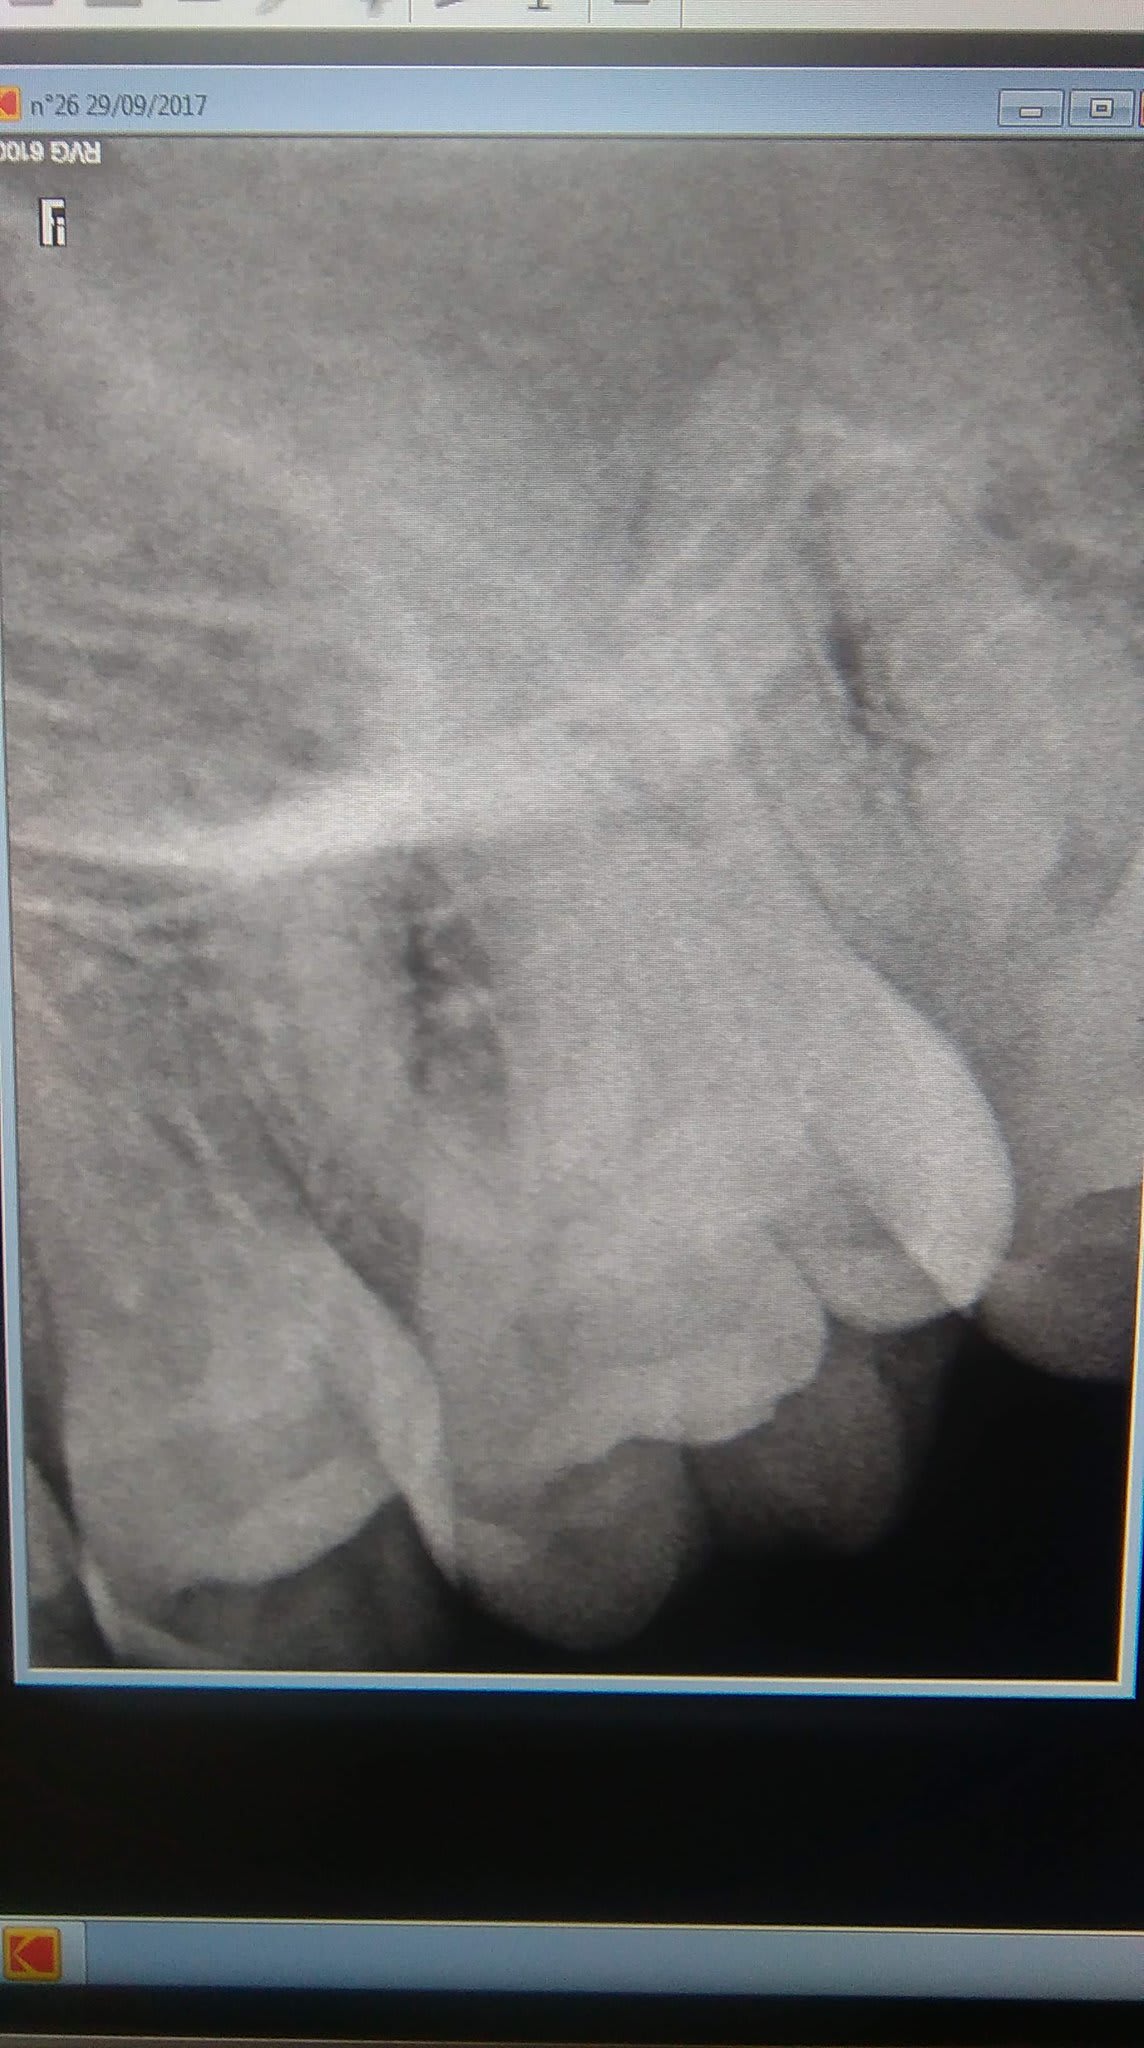

Désolé pour la qualité des radios (et photos), je ne sais pas si vous avez déjà eu un cas similaire.

Cette image radio du sinus ne peut-elle pas être en relation avec son opération dans l'enfance ?

les signes cliniques que tu décris évoquent la sinusite (pas forcément aigüe) par contre tes deux rétro ne permettent pas d'objectiver quoi que ce soit sur le sinus, excepté que les dents sont sinusiennes.